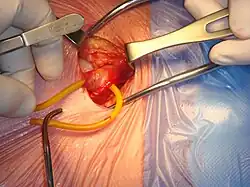

Reparación quirúrgica de una hernia inguinal derecha | ||

La cirugía de la hernia inguinal es una operación quirúrgica para la corrección de una hernia inguinal. No se recomienda la cirugía en la mayoría de los casos, y la espera vigilada es la opción recomendada.[1][2] En particular, la cirugía electiva ya no se recomienda para el tratamiento de hernias mínimamente sintomáticas, debido al riesgo significativo (> 10%) de dolor crónico ( síndrome del dolor post herniorrafia) y el bajo riesgo de encarceración o estrangulamiento (<0,2% por año).[3] Como consejo general si se opta por la cirugía, son más importantes la elección del cirujano y del hospital que la de una determinada técnica o material quirúrgico.[4]